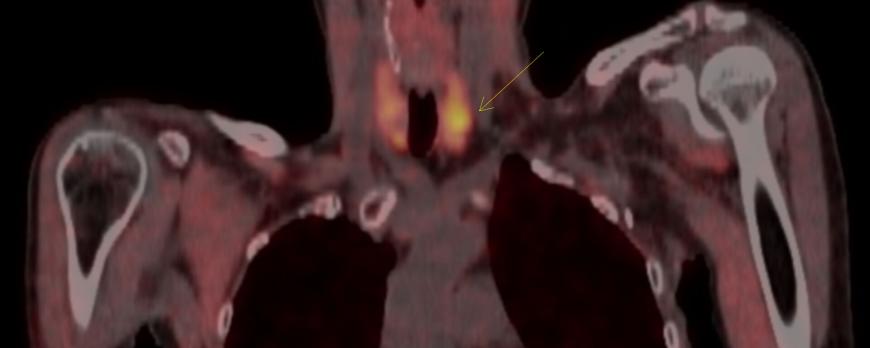

Tuberculose van het centrale zenuwstelsel doet zich in Nederland vooral voor bij mensen uit landen waar tuberculose endemisch is, of bij de ouderen die in hun jeugd besmet zijn geraakt. Een hiv-infectie en immuunsuppressie verhogen het risico. De ziekte kan zich uiten als een subacute meningitis, cerebrale tuberculomen of myelitis/spondylodiscitis. Tuberculeuze meningitis kan ernstig verlopen met sterfte of blijvende schade tot gevolg. Helaas wordt het vaak te laat herkend. Microbiologische diagnostiek van de liquor is ongevoelig, en dikwijls wordt er een waarschijnlijkheidsdiagnose gesteld op basis van het klinische beeld, typische liquorafwijkingen en epidemiologie. De behandeling bestaat uit maandenlange antimycobacteriële behandeling, adjuvante corticosteroïden en soms uit liquordrainage. Tijdens de behandeling kan een paradoxale verslechtering optreden met een toename van de koorts, inflammatie en neurologische en/of radiologische achteruitgang. Dit noopt tot verlengde of hernieuwde immunosuppressie. Als aan tuberculose van het centrale zenuwstelsel wordt gedacht, moet isolatie worden overwogen, omdat veel patiënten ook longafwijkingen hebben en daarmee besmettelijk kunnen zijn.